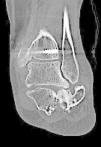

TC de calcáneo:obligatorio en todas las fracturas intraarticulares o con sospecha de serlas.

La clasificación de Sanders se basa en la valoración mediante TC coronal de la faceta posterior subastragalina, según el número de fragmentos de esta faceta desplazados más de 2mm2. Es una clasificación ampliamente estudiada y aplicada y, a pesar de que se ha criticado su alta variabilidad intra e interobservador, sigue siendo la clasificación de referencia3-6. Además, su valor pronóstico para predecir la artrodesis subastragalina ha sido demostrado (5,5 veces más probabilidad de terminar en artrodesis subastragalina una fractura Sanders IV que una Sanders II)7. Diferencia 4 tipos principales: